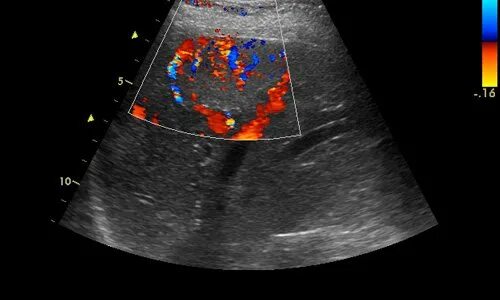

Что такое при цдк